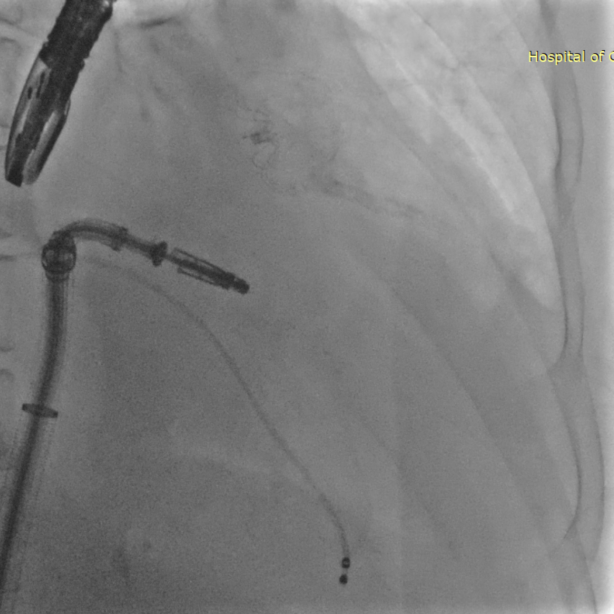

TEER手术过程

患者全麻下行TEER手术。向睿副主任团队穿刺患者右侧股静脉,在X线及食道超声指导下完成房间隔穿刺(视频4)成功获得3.95cm穿刺高度(图4)。再将加硬导丝送至左上肺静脉,20F股静脉扩张鞘充分扩张股静脉穿刺部位,沿加硬导丝将可操纵导引导管(SGC)送入左房。延SGC送入XTR夹子完成骑跨,使用M旋钮使夹子指向二尖瓣(图5)(视频5)。调整Mitraclip输送系统顺利到达二尖瓣目标位置,TEE指导下左房内完成弹道测试和Orientation调整(视频6)。缓慢将XTR夹子送入左室,并三维再次确认夹子轴向和反流位置,缓慢上提夹子使夹臂成功捕获瓣叶(视频7),Gripper Down夹持前后瓣叶并缓慢关闭夹臂(视频9),夹持后反流降至微量(视频10),二尖瓣平均跨瓣压差2mmHg(图6)。评估后将夹子释放。释放后反流微量夹子稳定。术后复查超声证实夹合组织充分,显示微量残余分流。术后二尖瓣平均跨瓣压差2mmHg,肺静脉多普勒波形恢复正常。手术时间持续约1.5小时。

图5:夹子送入左房骑跨后加M